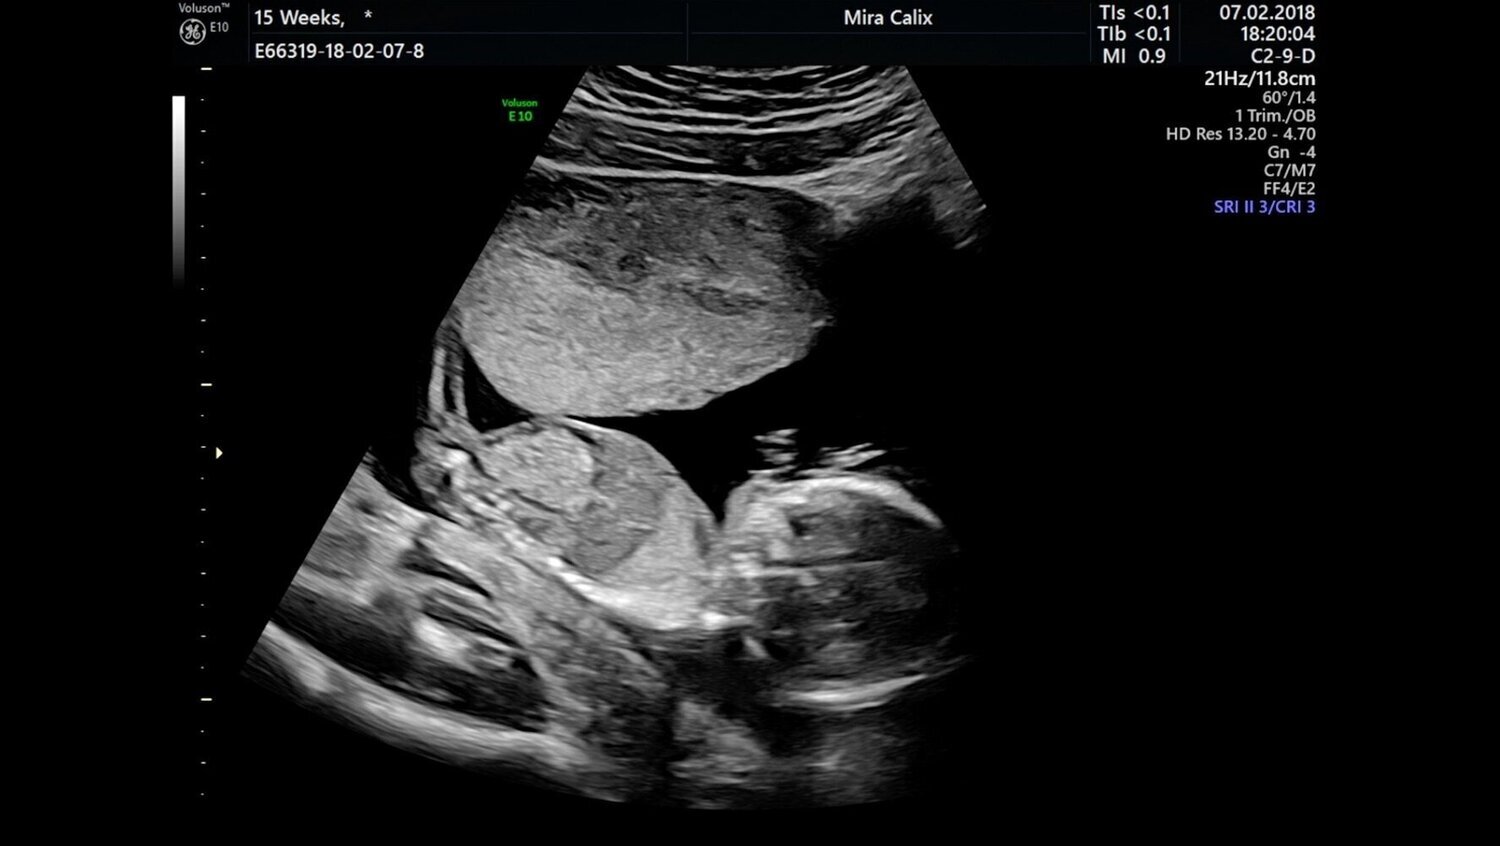

Mira Calix, 16 weeks (still), 2020. Image courtesy of the artist

In an apt nod to Mimosa House’s rebirth at its new space in Holborn after a year of postponements and uncertainty, the first work we encounter is a video of a foetal ultrasound scan projected onto the wall. In this work, 16 weeks (2018), Mira Calix uses sonification to translate the undulating movements of a foetus in the womb into a sound piece, melodious and classical in its tone. We see the image of the foetus warp and distort with the movement of the ultrasound wand. At times its form is recognisably human, at others it is more akin to the joining and dividing of the wax in a lava lamp. The sound piece, although played by a six-part orchestra and presented as a score next to the work, has no definitive climax or ending. It is a fluid shadowing of this alien movement, tracking the syncope of gestation; that liminal space between the downbeats of conception and birth.